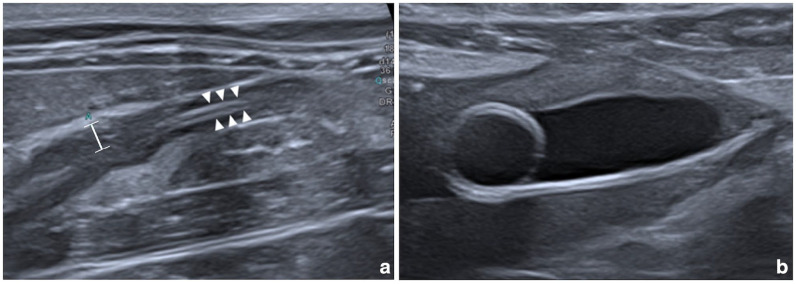

病例总结:一只2岁雌性绝育家短毛猫,有1周嗜睡和吞咽困难的病史,被送到兽医教学医院。体格检查发现严重的左肾肿大,高热和腹痛。腹部超声显示左侧输尿管因输尿管结石阻塞而扩张,并伴有明显的囊下积液。尿液分析显示尿液呈碱性,有鸟粪石结晶。肾盂及膀胱尿液培养假中葡萄球菌阳性。怀疑因存在产脂细菌而感染鸟粪石输尿管结石。通过输尿管切开术取出输尿管结石,并顺行放置临时输尿管支架。红外光谱结果显示为纯鸟粪石尿石症。手术后35天通过膀胱镜取出支架。在6个月的随访中,这只猫仍然表现良好。相关性和新信息:据作者所知,这是猫因肾盂肾炎导致鸟粪石输尿管结石的第一例。

Case summary: A 2-year-old female spayed domestic shorthair cat with a 1-week history of lethargy and dysorexia was presented to a veterinary teaching hospital. Physical examination identified severe left nephromegaly, hyperthermia and abdominal pain. Abdominal ultrasound revealed a left ureteral dilation due to obstruction by a ureterolith, associated with marked subcapsular effusion. Urinalysis showed alkaline urine with crystals of struvite. Culture of urine from the renal pelvis and the urinary bladder was positive for Staphylococcus pseudintermedius. An infected struvite ureterolith due to the presence of urease-producing bacteria was suspected. The ureterolith was removed via ureterotomy and a temporary ureteral stent was positioned in an antegrade fashion. Results of infrared spectroscopy showed pure struvite urolithiasis. The stent was removed via cystoscopy 35 days after surgery. The cat was still doing well at the 6-month follow-up.